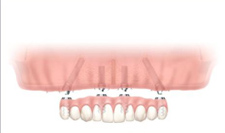

All-on-4 では、臼歯部にインプラントを30-45°傾斜させて埋入することにより、下顎で4本、上顎で4-6本のインプラントで補綴を支持することができます。

インプラント埋入(上顎)

【術前】